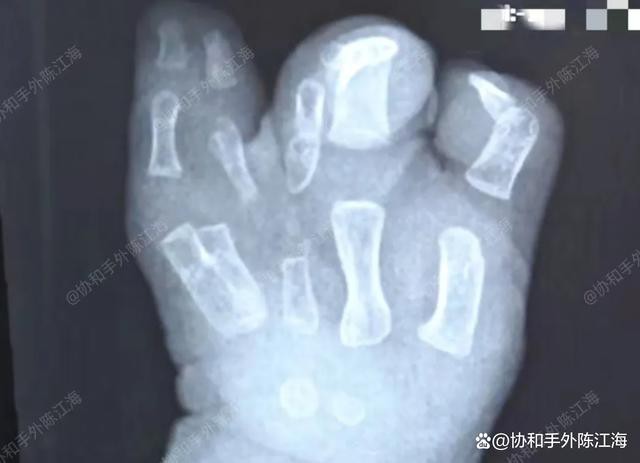

Die Finger der linken Hand des Kindes waren fest miteinander verwachsen, und abgesehen vom Daumen schienen die übrigen Finger miteinander verwachsen zu sein. Die Situation war komplex, sodass wir die Trennung der verwachsenen Finger letztlich in zwei Schritten durchführten.

Präoperatives Röntgen

Im ersten Schritt wurden drei Finger abgetrennt, im zweiten Schritt die restlichen zwei Finger. Auf diese Weise konnten die Finger des Kindes schrittweise abgetrennt werden, was sowohl optisch als auch funktionell sinnvoll ist.